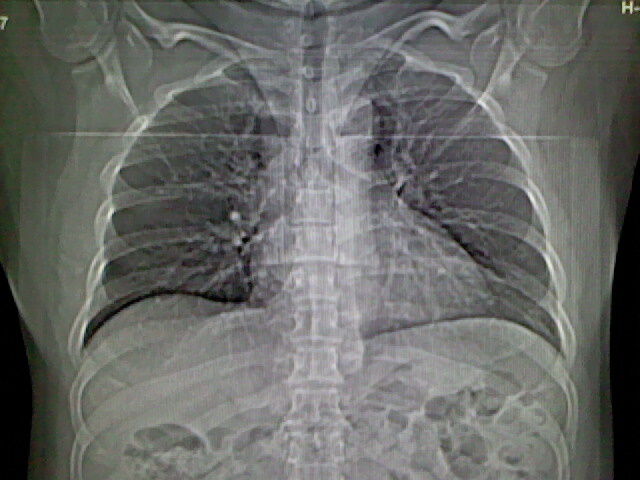

标题: CT17932:临床怀疑肺栓塞

男,34岁,自觉右侧胸痹,胸闷3天余

两肺纹理增多,余未见明确异常。

肺纹理分布较均匀,暂不提示肺梗塞

右侧肺动脉似见密度稍低影,请在机器的薄层上再看看有没有充盈缺损。